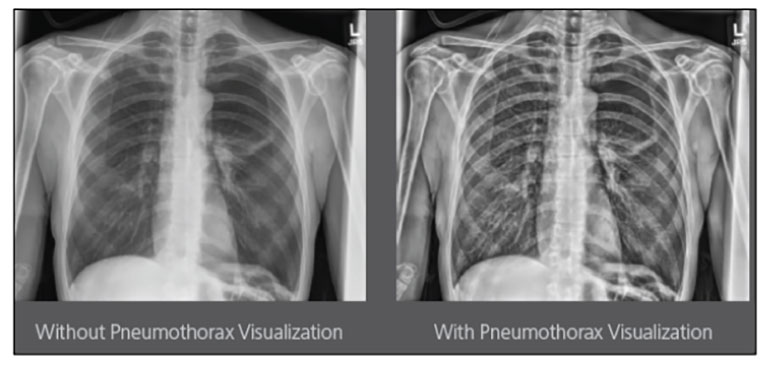

CARESTREAM Image Suite V4 MR11 has set a new standard for workflow efficiency, offering a robust set of features and functionalities to enhance clinical confidence in healthcare professionals. Using an auto-generated companion image from a single exposure, leverage a range of image processing options to increase diagnostic accuracy and enhance patient care.

Carestream Introduces New Software Update to Boost Diagnostic Accuracy

Carestream today announced the latest update to its Image Suite V4 Software, MR 11: a series of enhancements to help improve customer confidence and increase diagnostic accuracy [...]